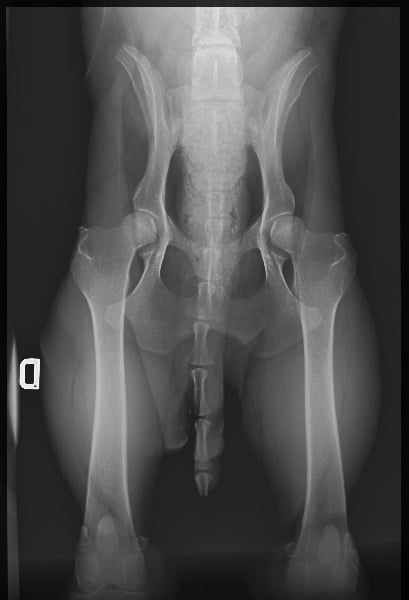

| Tares |

DENTITION COMPLETE EN CISAILLE : DENTITION COMPLETE EN CISAILLE INDEMNE DE DYSPLASIE : DYSPLASIE A PAS DE MANQUE DE DENTS : DENTITION COMPLETE |